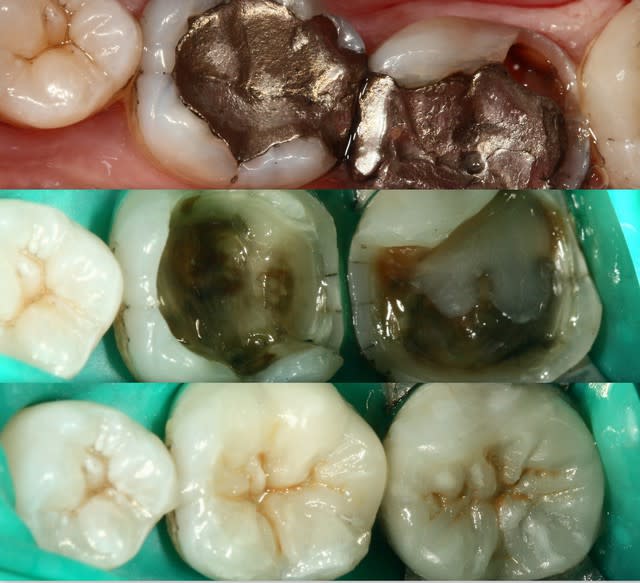

chipoundine

28/11/2013 à 23h40

tiens c'est bizarre , sur la dernière photo de cingulum (magnifique travail d'ailleurs) , la dent est toujours sur l'arcade alors que le joint semble être juxta voir sous gingival. Il m'a semblé avoir lu plus haut qu'un joint en compo ça se carie automatiquement au bout de cinq ans....

Allez cingulum , arrête de nous faire marcher, fais peter la radio avec la reprise de carie, l'endo, l'IC et la CCM!

sympa le boulot chipoundine;

perso, sur la 24 j'aurais abaissé les limites périphériques pour faire une couronne collée Emax (meme prix pour toi, meilleur remboursement du patient, meilleur longuévité que l'onlay à plat car opposition de parois, collage sous digue toujours posible), tu aurais juste à poser la digue unitairement.

bon courage et continue dans le collage.

Ben alors j'ai un cas là justement : je fais quoi? Onlay ou Couronne?

Dent vivante, CVI renforcé après la taille en coiffage attente de 3 semaines avec pansement pour être sûr, RAS dent toujours vivante quand je l'ai revu aujourd'hui.

Aujourd'hui : retouche du CVI puis (première photo au stade du mordançage) compo pour le core build-up, pansement.

Les photos sont pas top mais pour le moment je fais avec ce que j'avais sous la main...

Qu'est-ce que je fais pour la suite du coup? Onlay ou Couronne?

PS. On ne voit pas bien la différence à la radio avant-après... Désolé.

Perso je penche pour la couronne...